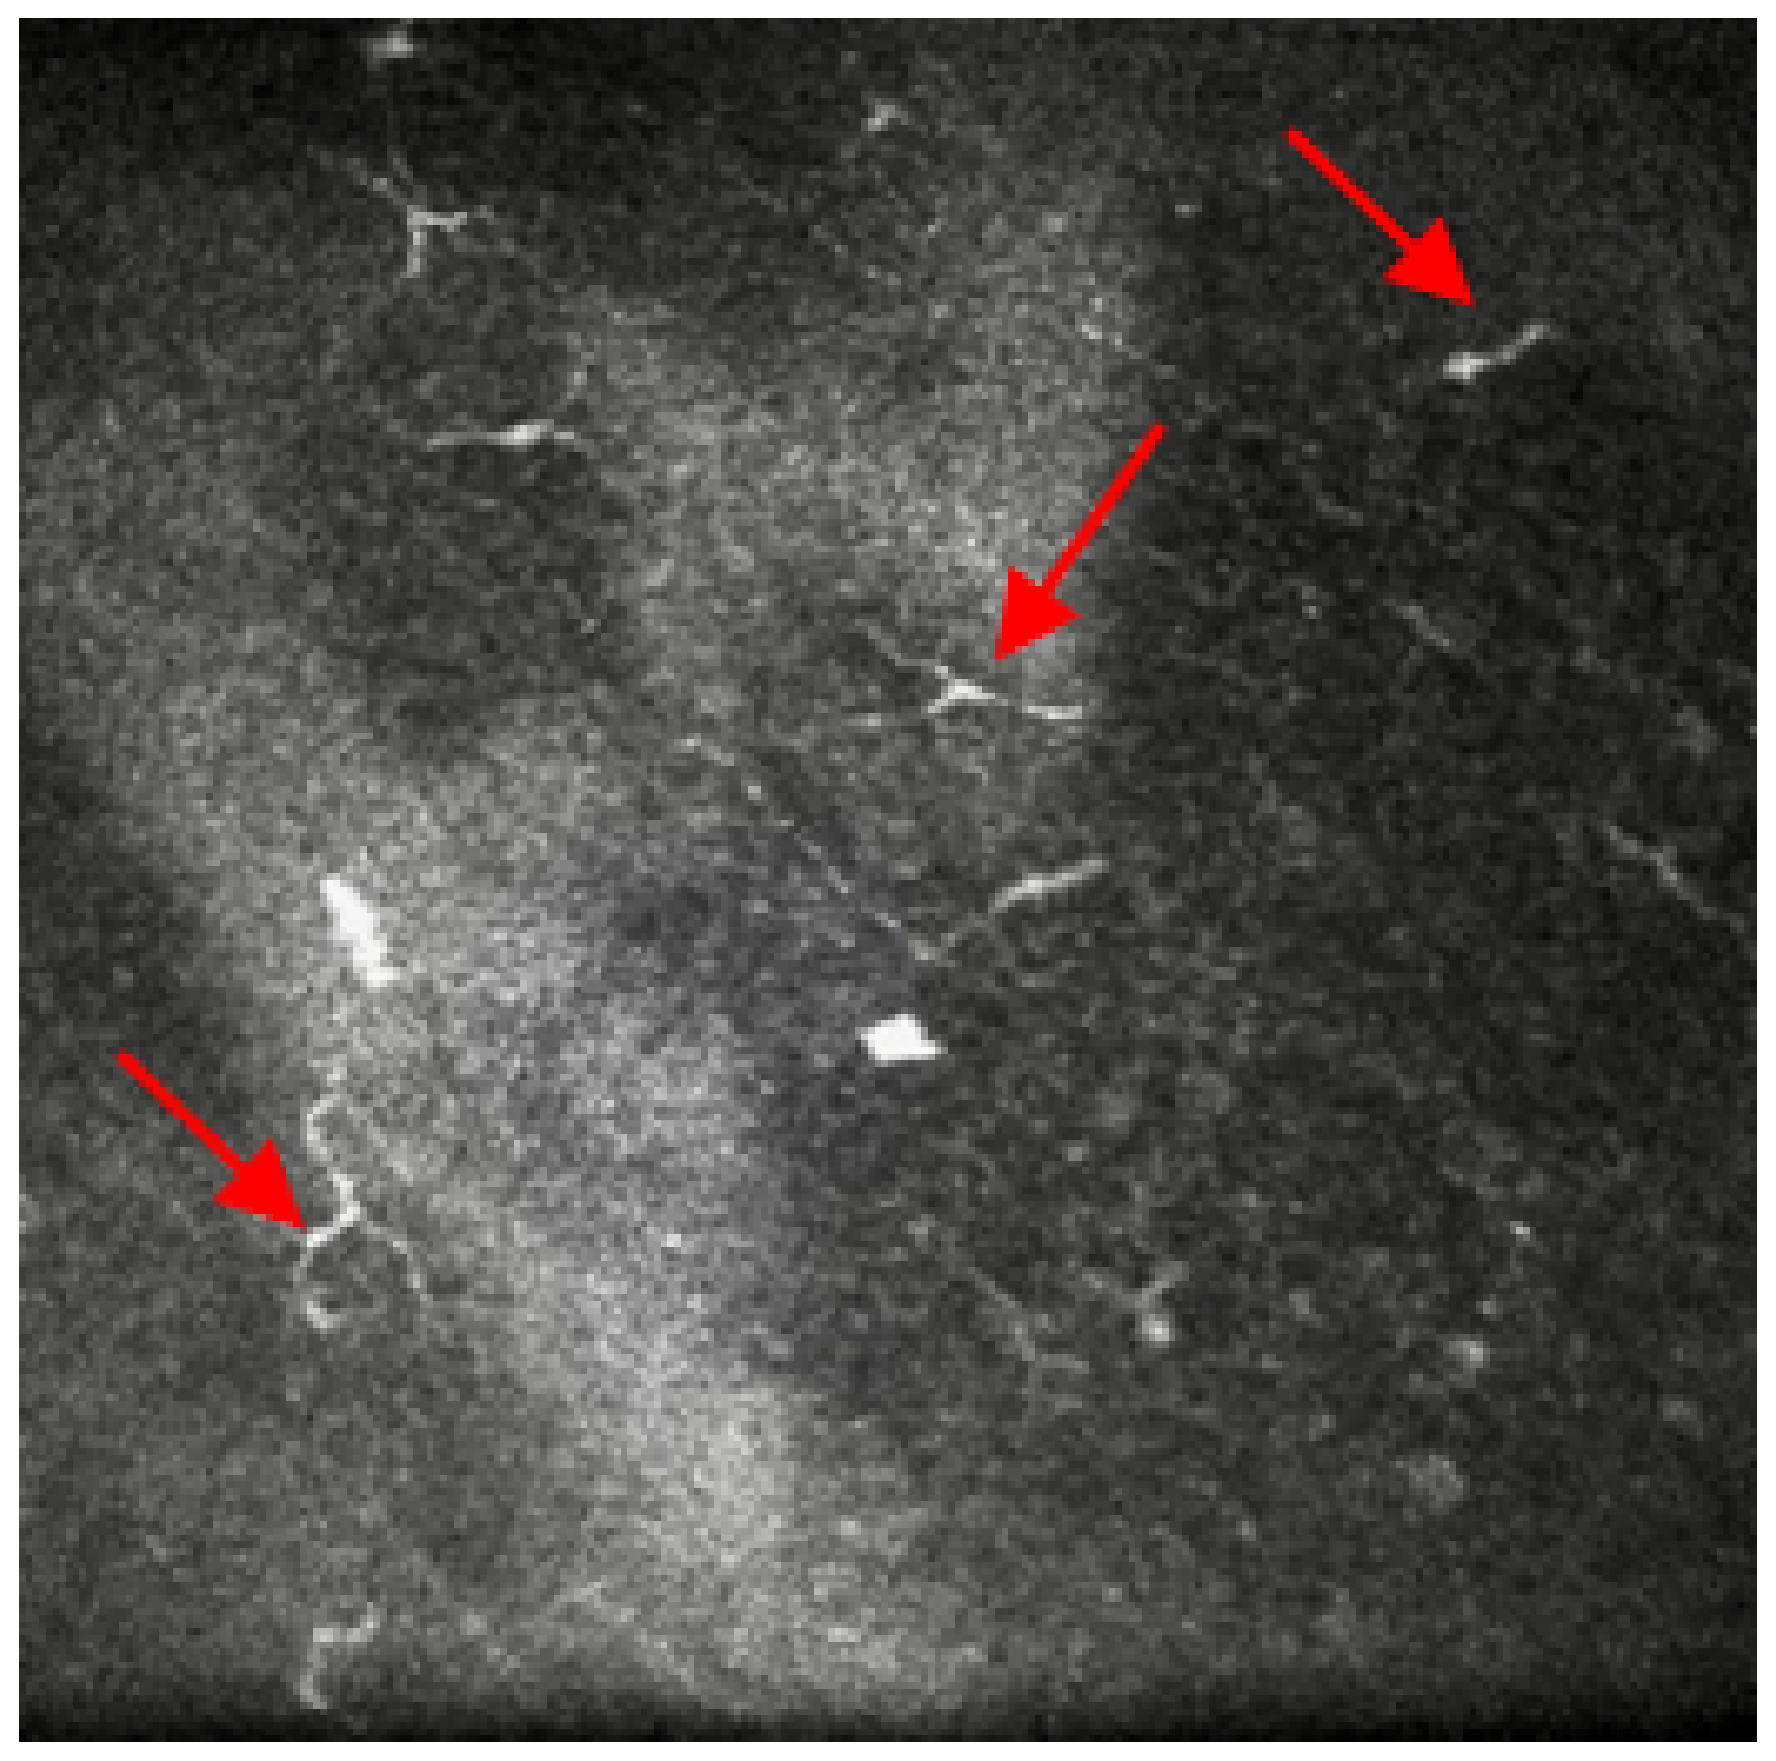

2. Case Reports

2.1. Case 1

2.2. Case 2

2.3. Case 3

3. Discussion